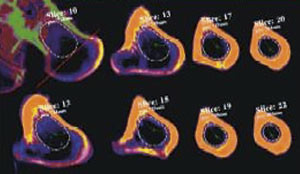

Vi har et nært samarbeid med miljøet i Trondheim. Røntgenavdelingen i Arendal gjør en tredimensjonal CT-fremstilling av pasientens øvre femur, dataene blir sendt elektronisk til Trondheim, og femurkomponenten fremstilles deretter i en datastyrt produksjonsprosess (fig 1). Protesen er laget av titan. Det tilstrebes at protesen har optimal kontakt til 1,5 – 2 cm nedenfor trochanter minor, det samme område er belagt med hydroksyapatitt på en porøs overflate (fig 2). Collumanteversjonen er standardisert til 10°. Operatøren får tilsendt operasjonsdokumentasjon fra produsenten. Det er ut fra femurkomponentens halslengde og halsvinkel at operatøren kan velge medial offset, fremre offset (fig 3) og bestemme ønsket beinlengde (fig 4). Deretter ferdigstilles den individtilpassede hofteprotesen. Det følger med en reseksjonsmal for collumkuttet, og instruksjon om hvordan malen skal stilles inn for den enkelte pasient. Det følger også med 1 – 2 spesialtilpassede rasper for preparering av femurkanalen (fig 5). Kun femurprotesen er individtilpasset, for acetabulum benyttes standard acetabularproteser.